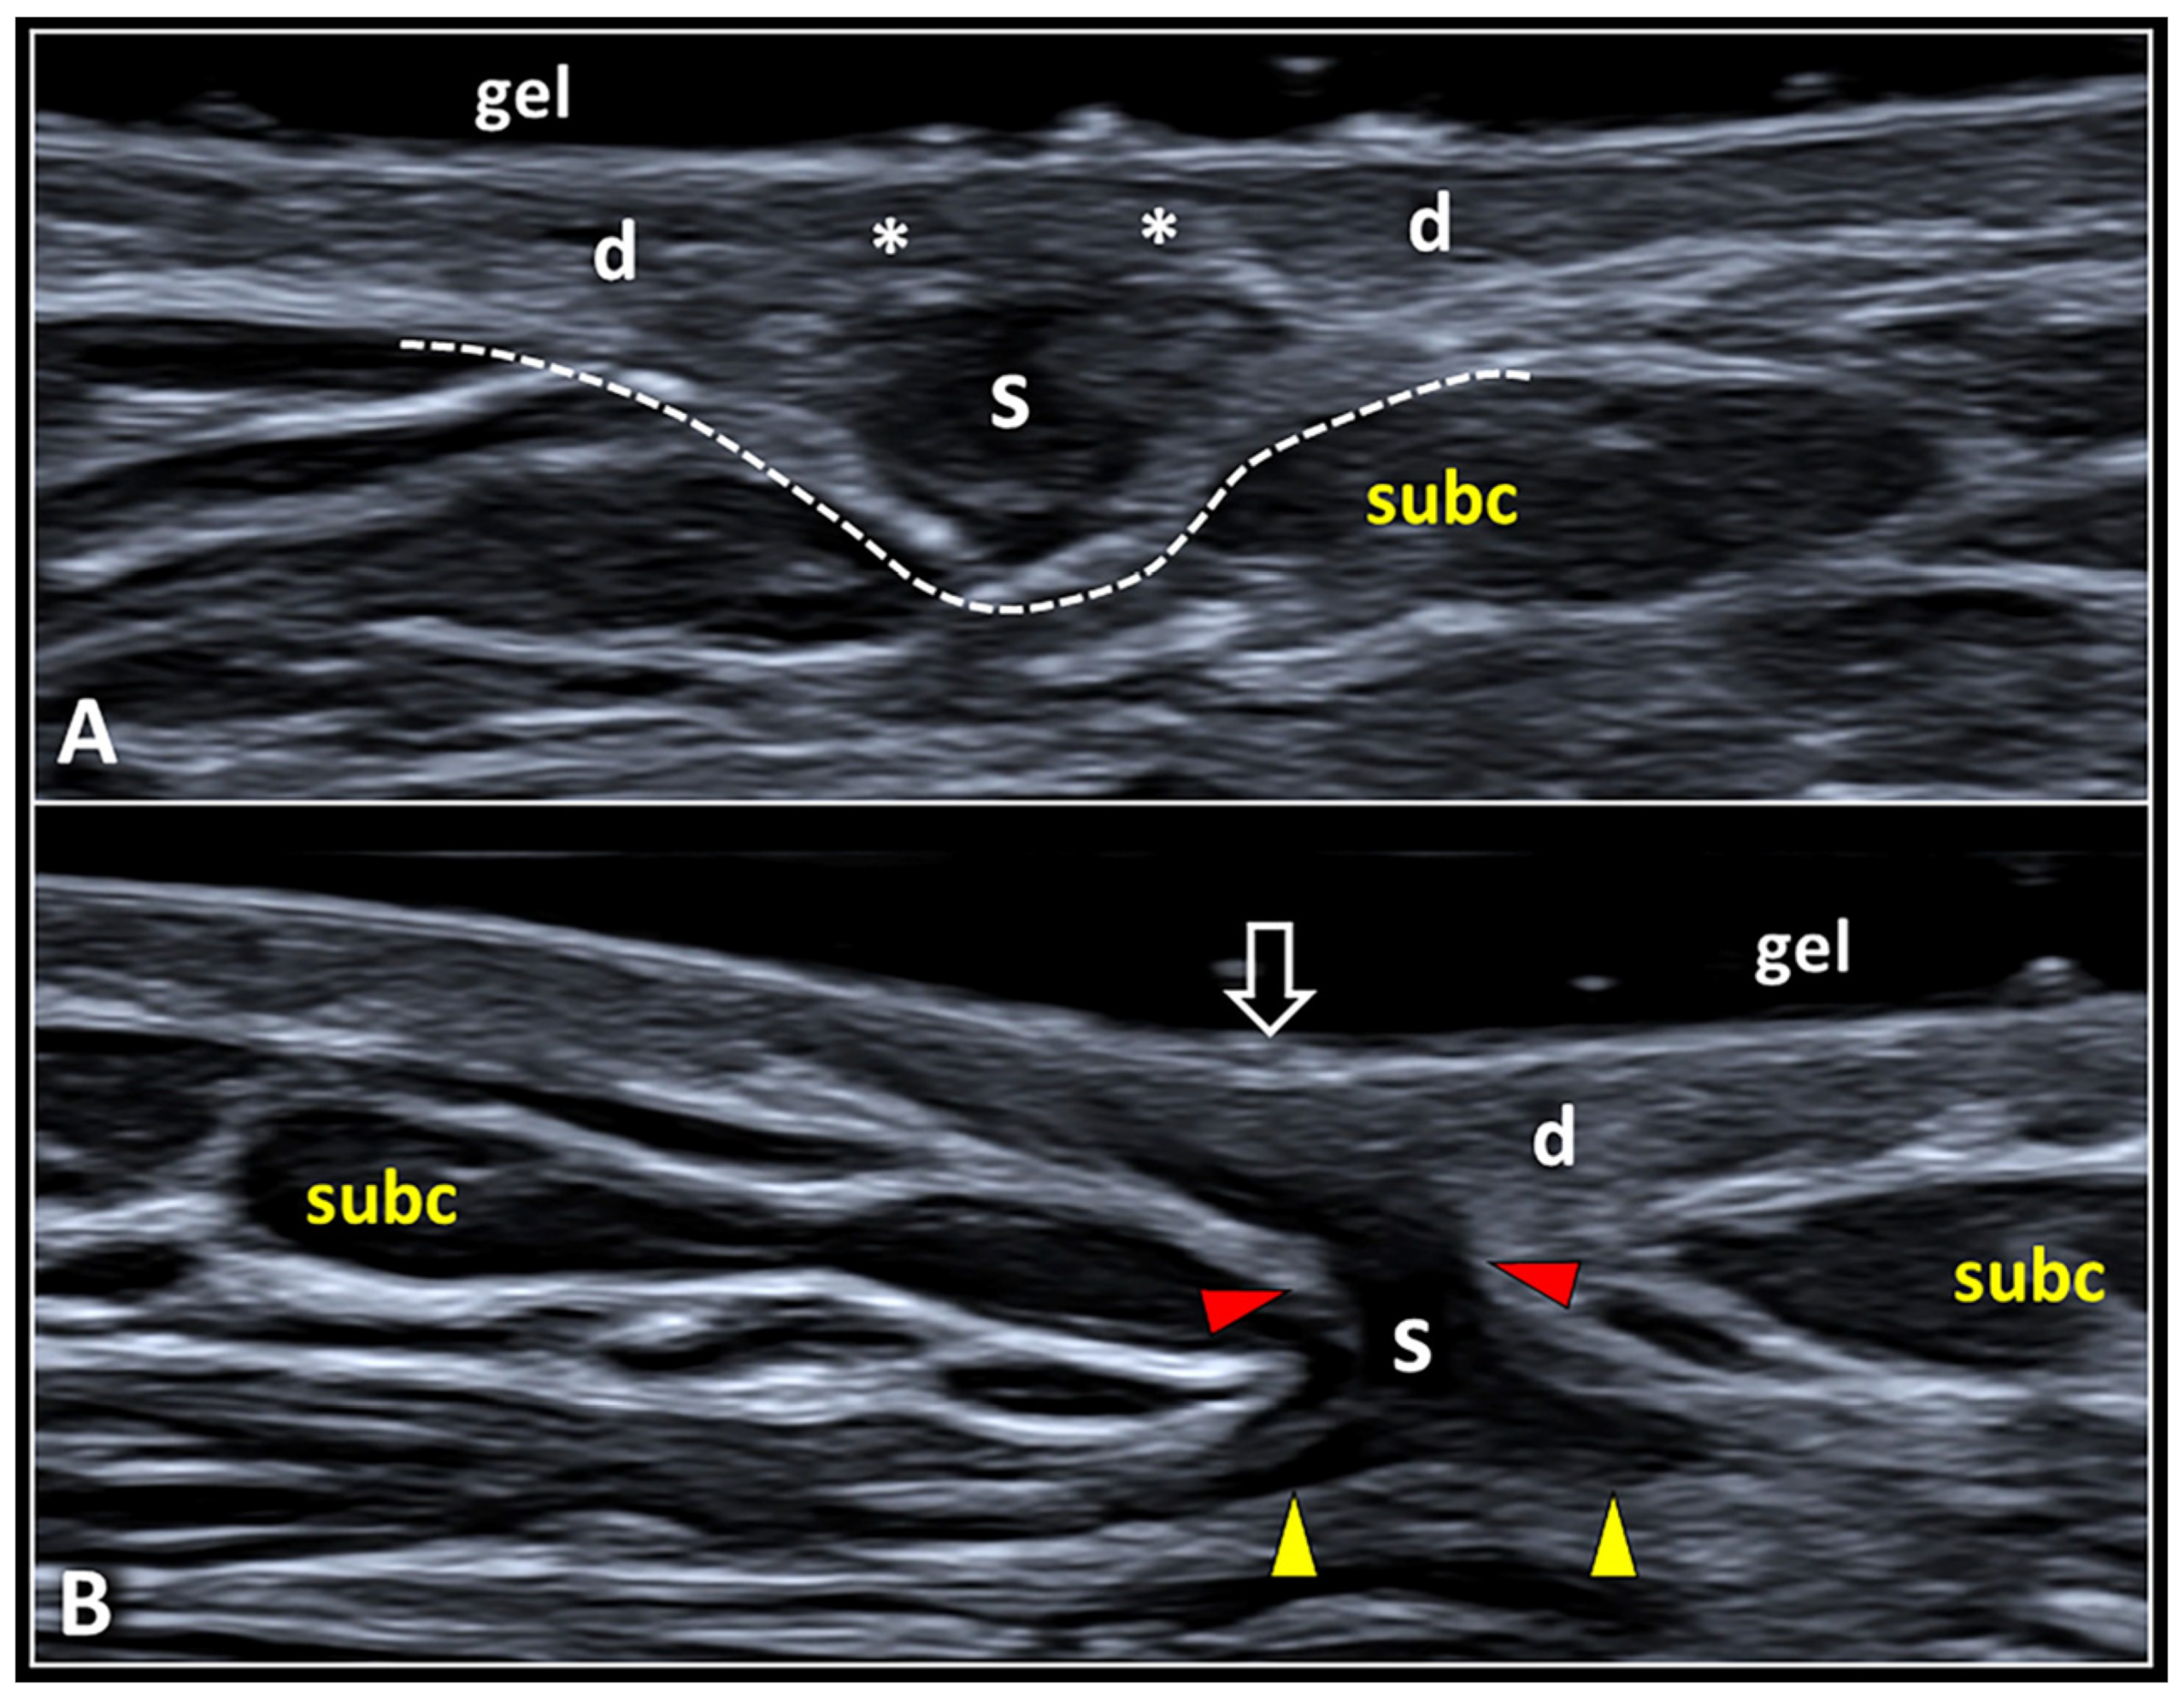

Figure 7.

Dermo-hypodermal and dermo-epidermal interfaces. The skin scar may present an expansive pattern (Ep) compressing the underlying subcutaneous fat tissue (S) or an infiltrative pattern (Ip) with distal expansions that penetrate inside the subcutaneous layer (S) (A). Detachment of the epidermis (E) from the underlying dermis (D) can occur near the scarring tissue (S)—i.e., the dermo-epidermal dissociation (B).

In this sense, the scar tissue with an expansive pattern shows a mass effect pushing the surrounding soft tissues without retraction. In some patients, the epidermis and the superficial portion of the dermis may develop a complete histological healing “hiding” the scar in the deeper layers (Figure 8). In these cases, inspection during the traditional physical examination may underestimate the real size/extension of the scar tissue whereby US examination becomes necessary to identify and measure the skin scar. Of note, the continuity of hyperechoic DHI must be confirmed for the entire extension of the skin scar, considering the fact that the infiltrative process toward the underlying subcutis may selectively involve the central or more lateral (peripheral) portion of the scarring tissue.

Expansive vs. infiltrative pattern of SSs. A globular shaped scar (S) originating from the deep portion of the dermis (d) compresses the underlying subcutaneous fat tissue (subc) preserving the histological continuity of the dermo-hypodermal interface (white dotted line) (A). Note that the superficial portion of the dermis (white asterisks) is not involved in the fibrotic involution (A). An irregular shaped scarring tissue (S) interrupts the dermo-hypodermal interface (red arrowheads) and shows distal expansions (yellow arrowheads) infiltrating the subcutis (B). Interestingly, this type of scar (S) shows a contractile behavior mechanically tensioning the overlying epidermis (void arrow) and distorting the surrounding subcutaneous tissue (subc) (B).

The infiltrative pattern, instead, usually presents a scarring tissue irregular in shape that interrupts the DHI—penetrating within the subcutaneous fat and mechanically distorting the surrounding tissue. The hypoechoic scar crosses the hyperechoic DHI and generates thin expansions insinuating in between the adipocytes of the subcutis (Figure 7). The sonographic pattern obtained with high-frequency US transducers accurately matches the aforementioned histopathological features of HS, with fibrotic digitations advancing within the subcutaneous tissue (Figure 1). In these cases, the concave deflection of the epidermis and the spatial disorganization of the fat lobules and fibrotic scaffold of subcutis can be considered as indirect sonographic signs of scar retraction. If clinically indicated, in patients with the infiltrative pattern, a second-line diagnostic tool such as biopsy may be necessary to accurately define the histopathological features of the mass.